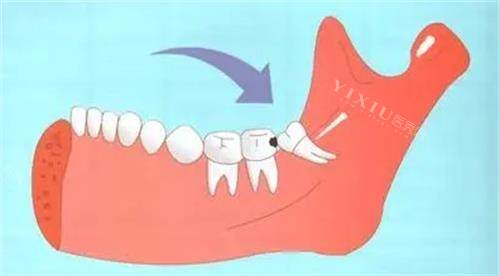

等了没一会儿,就轮到我见孙医生了。他看起来特别可靠,说话也很温和,详细问了我智齿发炎的情况,还仔细检查了口腔。他一边看一边给我解释,说我的两颗智齿都是横着长的,顶到了前面的牙齿,不仅容易发炎,时间长了还会把前面的牙顶坏,所以建议尽快拔掉。我当时就问:“拔牙会不会特别疼啊?” 孙医生笑着说:“放心,我们会用适合的麻醉方式,整个过程你不会有明显痛感,术后也会详细告诉你注意事项,帮你顺利改善。” 听他这么一说,我心里踏实多了。